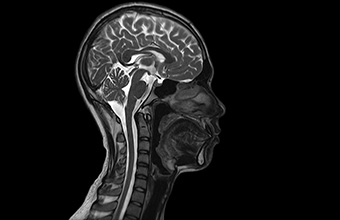

Neurološka snimanja

Neurološka MR snimanja glave i kralježnice istražuju od mogućih tumora mozga do hernijacija diska kralježnice visoko kvalitetnim morfološkim i funkcionalnom tehnikama.